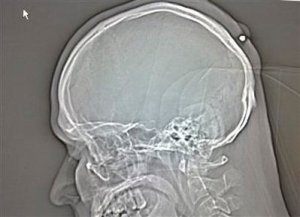

Check out this X-Ray of the bullet in his head!!

The discovery was made when he recently went to the doctor to have a lump examined. Police are not treating the incident as malicious: “It may have been a shot fired up in the air which entered his head on the way down.”